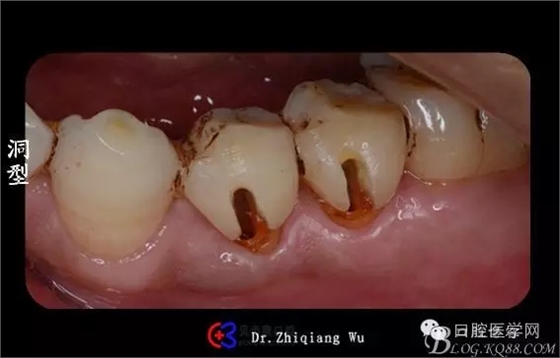

檢查:34頰側(cè)楔狀缺損,探(酸),冷(++),叩(±)

35頰側(cè)楔狀缺損,探(-),冷(-),叩(++),可探及穿髓孔

X線片顯示:34,35牙頸部大面積陰影,35根尖少量陰影